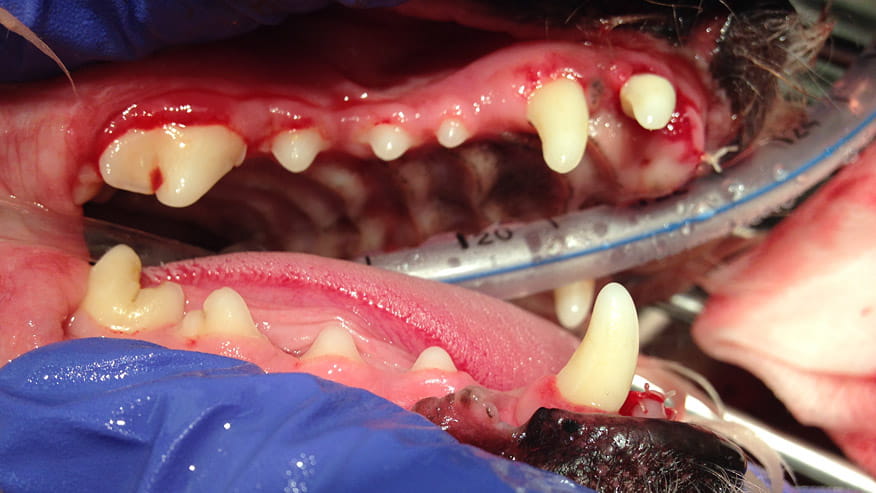

• VCA Wakefield Animal Hospital Dental Care

Dogs and cats don't often get cavities. But they do frequently suffer from other types of dental disease. Periodontal or gum disease, in fact, is the number one illness found in both dogs and cats.... Read more

• Our hospital offers dental radiographs (x-rays) as part of our dental care services. Specifically designed dental radiology equipment allows your veterinarian to view structures that lie below the gum line. The location of tooth root infections, the extent of periodontal bone loss and the identification of bone cysts and tumors can be identified using dental x-rays.... Read more

• VCA Wakefield Animal Hospital Dental X-Rays

Our hospital offers a variety of Dentistry Services. At your pet's yearly examination it may be determined that they require a dental cleaning. Routine veterinary dentistry involves prophylaxis (teeth cleaning), polishing and a full oral examination.... Read more